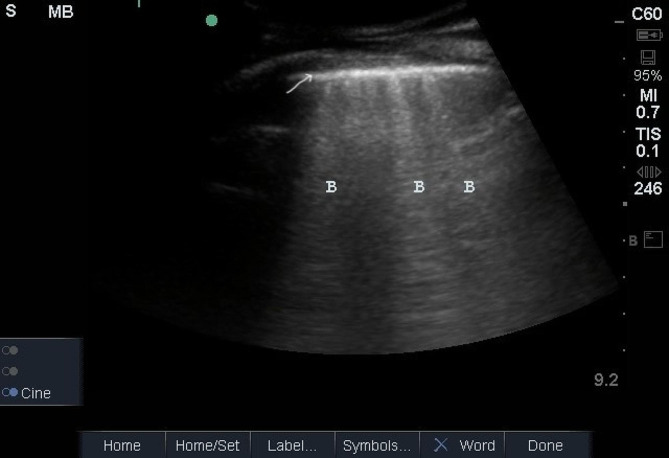

Results: Forty-eight patients (25 women (52%), mean age 75 years, standard deviation (SD) ± 7.7 years) were enrolled in the study. We detected severe B-lines (≥ 30) in 13 (27%) patients and moderate B-lines (15-30) in 33 (68.6%) patients. The number of B-lines increased significantly with the severity of New York Heart Association (NYHA) functional classes (Fig. 1). The B-line count was 14 ± 13 in NYHA class I patients, 20 ± 20 in class II patients, and 44 ± 35 in class III patients (p < 0.05, rho = 0.384). The number of B-lines was correlated with the E/E' ratio (R = 0.664, p < 0.0001) and the proBNP level (R = 0. 882, p < 0.008). We found no significant correlation with the LVEDP or LVEF. The LVEDP correlated well with the E/E' ratio (R = 0.491, p < 0.001) but not at all with E/A, DT, or LAVI. All patients had an elevated LVEDP > 12, with a mean pressure of 26 mmHg, a minimum of 13 mmHg, and a maximum of 45 mmHg, with an SD of 7.85.